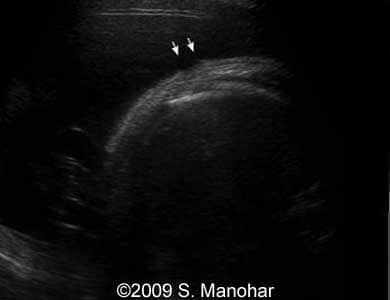

Images 8, 9, 10, 11, 12, and 13: The images shows discontinuities of the skin surface (arrows), a typical sign of the Harlequin type ichthyosis.

8-b

8

9-b

9

10-b

10